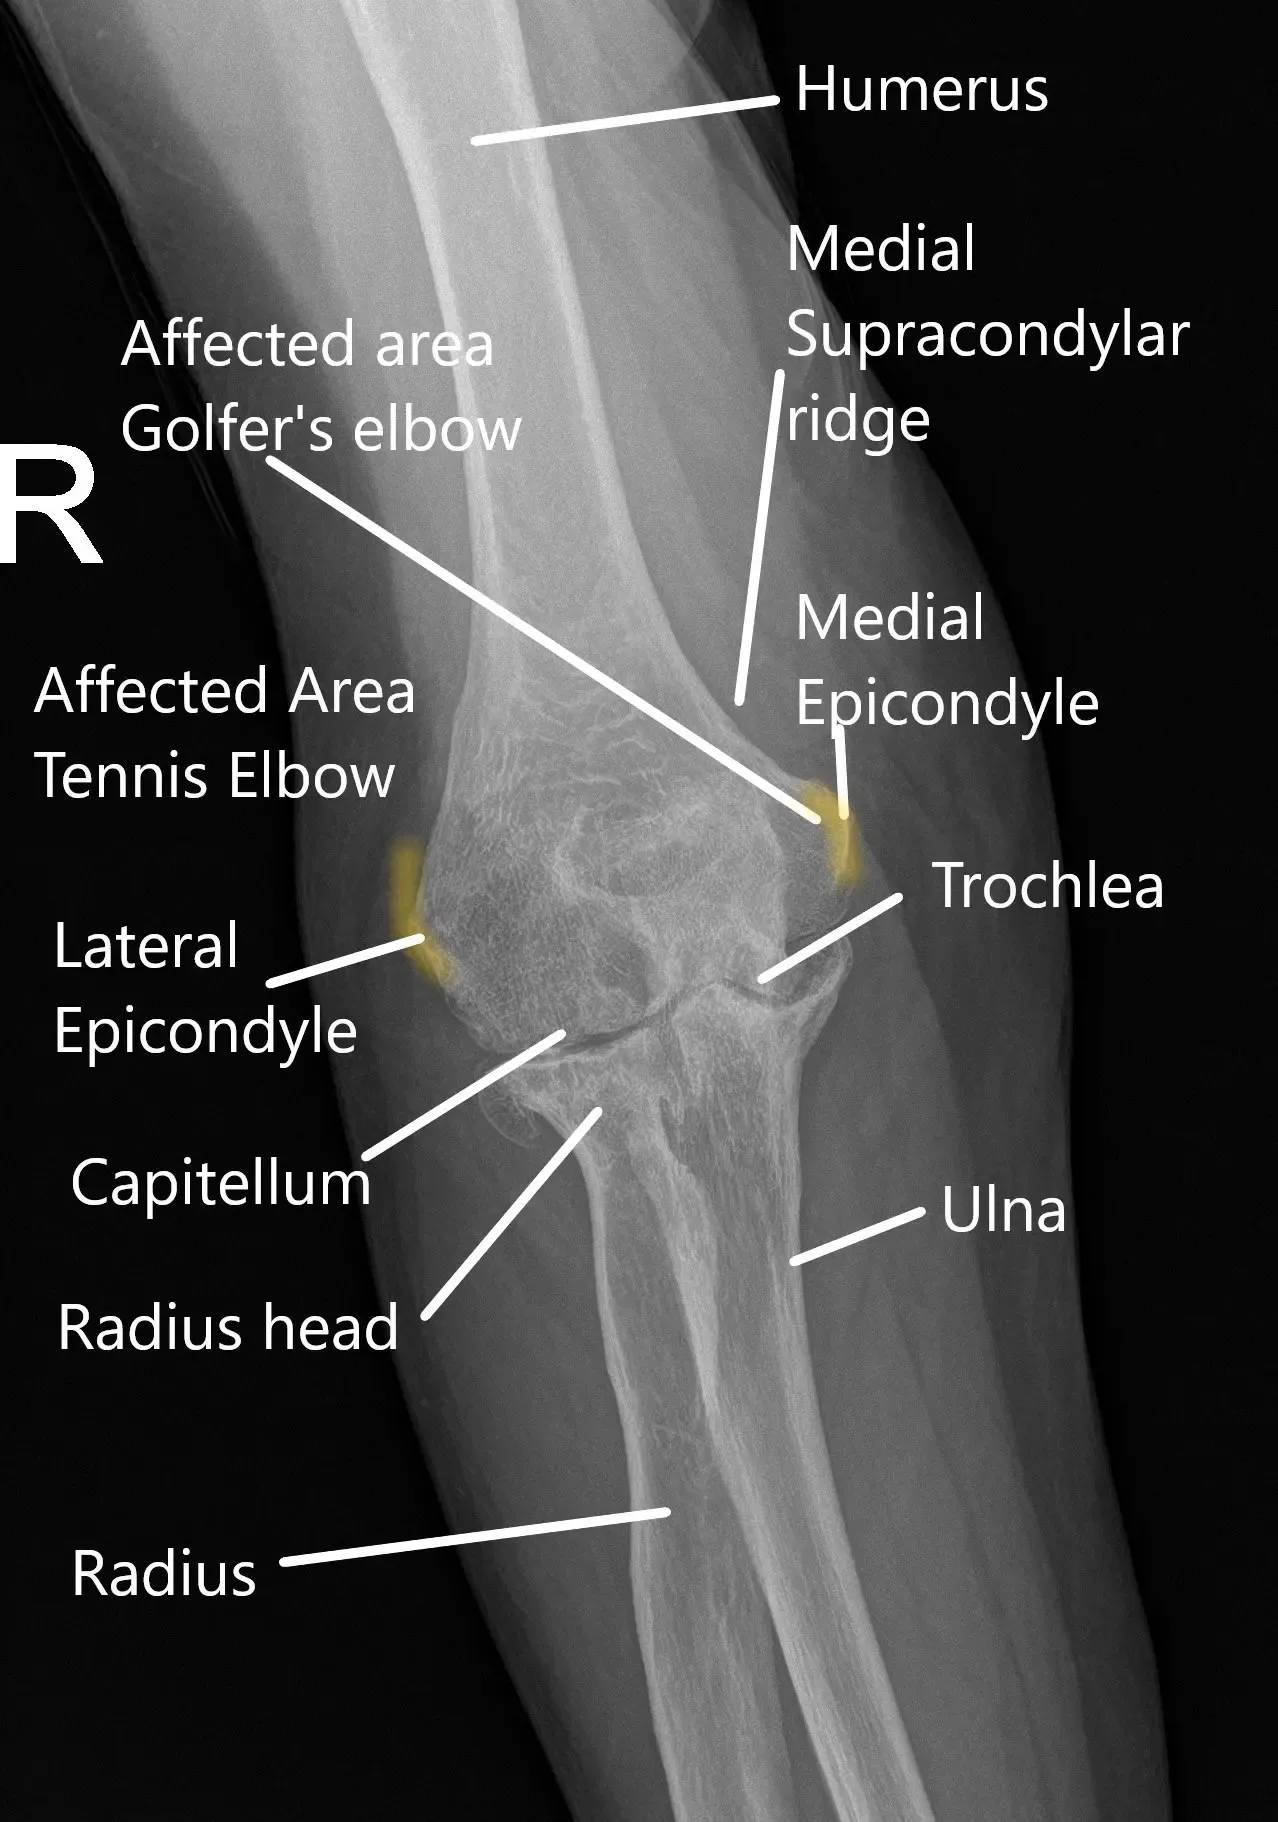

Radiografía de la muñeca que muestra varias partes de la articulación del codo.

La articulación del codo está formada por el extremo inferior del hueso del brazo superior y los dos huesos del antebrazo. Los huesos de la articulación se mantienen unidos a través de tejidos duros conocidos como ligamentos. Los tendones unen los músculos a los huesos. Los músculos ayudan en los distintos movimientos de la articulación.

Los extremos del húmero, el cúbito y el radio que forma la articulación están cubiertos por cartílago articular. El cartílago articular es un tejido blanco y liso brillante que ayuda al deslizamiento suave de la articulación. Hay varias bursas que recubren la articulación y reducen la fricción cuando distintas estructuras cruzan el codo.

Ciertos trabajos que requieren una fuerza rotacional excesiva mientras el brazo está recto pueden causar codo de tenista. Como su nombre indica, la condición afecta a los tenistas debido a una técnica inadecuada. Los tendones adheridos en el lado exterior del codo se inflaman e hinchan. Otros trabajos en riesgo son fontaneros, carpinteros, pintores y deportes de raqueta.

De manera similar, la inflamación de los tendones adheridos en el lado interno del codo puede causar epicondilitis medial o el codo del golfista. Además del golf, otros deportes que implican el lanzamiento también pueden provocar epicondilitis medial. La condición también puede afectar a niños pequeños en crecimiento conocidos como codos de los pequeños ligas.